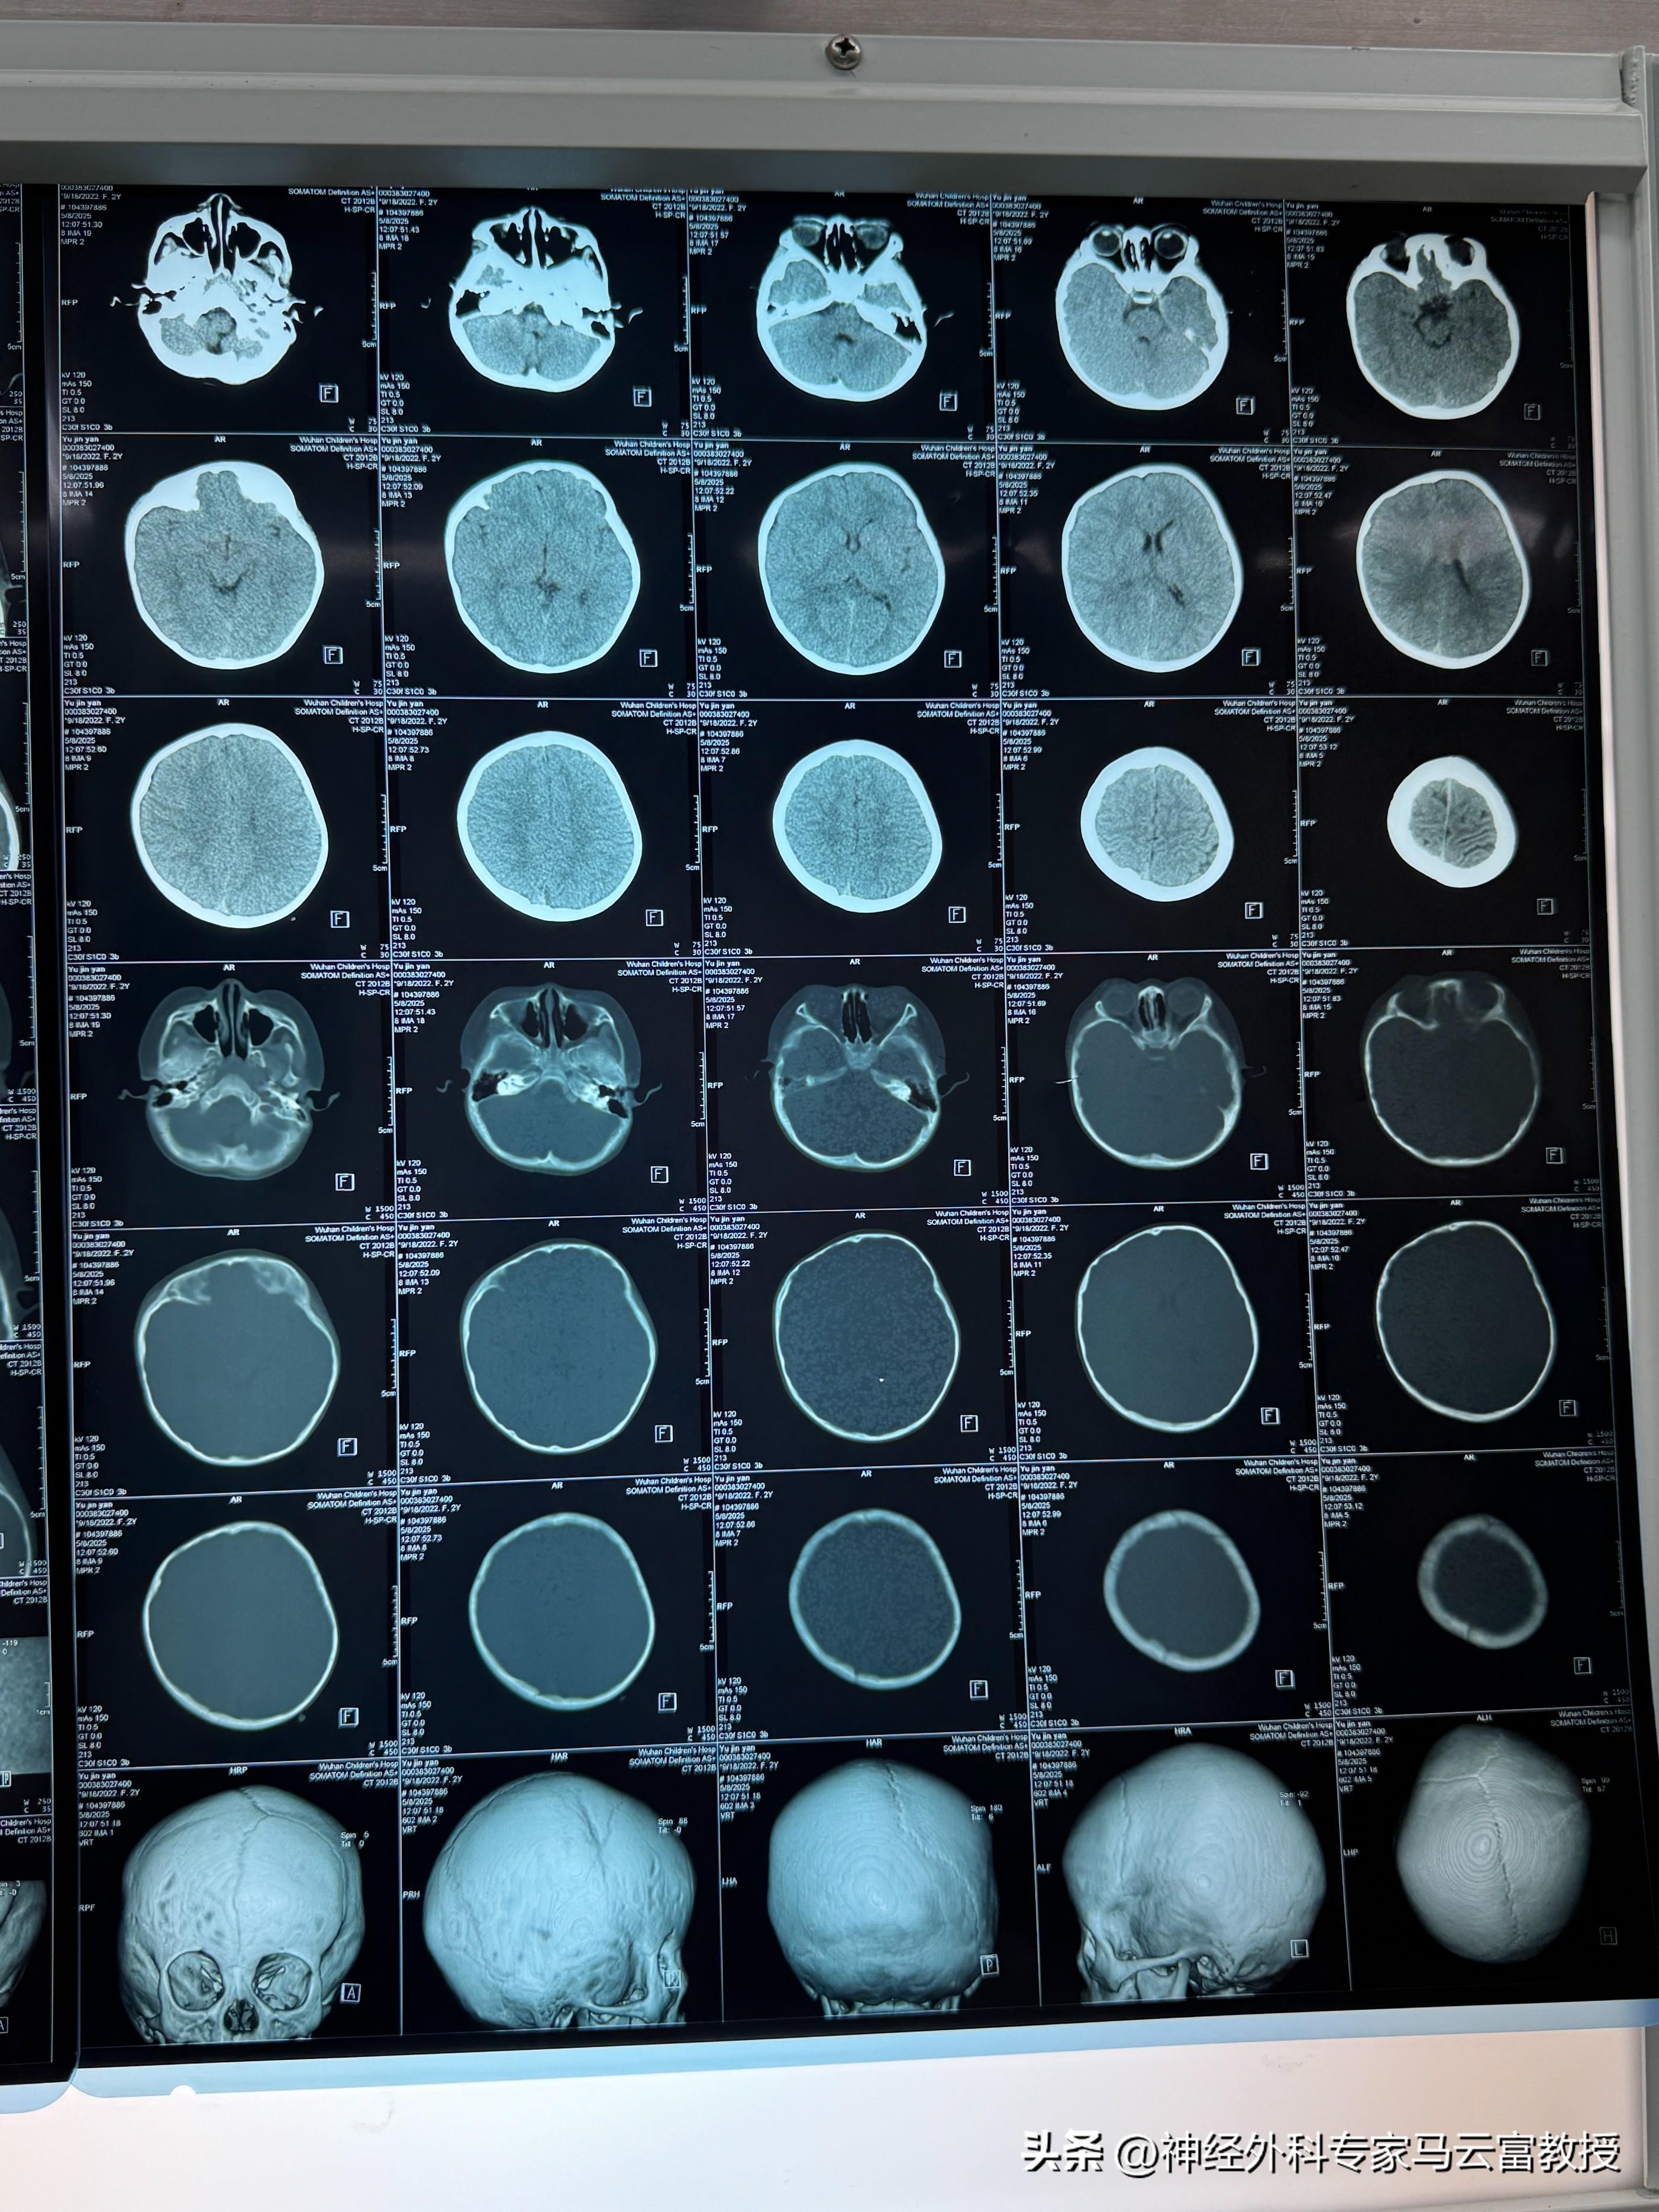

患兒術前顱腦CT

接診後,馬雲富教授高度重視,立即聯合夏星副主任組成專項診療團隊。考慮到患兒年齡小、顱骨結構特殊,且需同時解決顱縫早閉與眼眶骨畸形問題,團隊進行了多輪病例研討。爲實現精準矯治,團隊提前利用先進技術爲小魚進行顱腦內骨塊三維重建與個性化設計,反覆模擬手術流程,力求在矯正顱縫早閉的同時,最大程度修復右側眼眶骨畸形,還原顱骨與眼眶的正常生理形態。